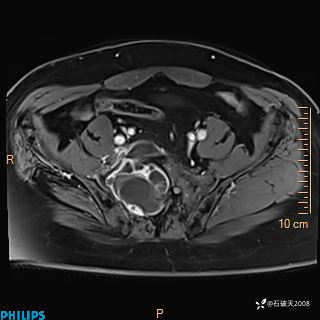

现病史:7个月前患者因骶尾部占位就诊于北京大学人民医院,MRI示:骶骨右侧及右骶前占位,考虑骨巨细胞瘤可能,动脉瘤样骨囊肿可能,神经源性肿瘤待排。行手术治疗,术后病理回示:XXXXX。术后给予对症治疗,具体不详,恢复良好。近几个月反复出现发热,伴骶尾部不适,多次住院给予对症治疗,2天前患者无明显诱因再次发热伴骶尾部不适,无大小便失禁,为求进一步治疗,遂门诊来我院,在门诊初步检查后,以“骶尾部肿物”为诊断收入我科。入院来患者神志清,精神一般,饮食睡眠可,大小便无明显异常,体重无下降。

2023年3月份MRI影像

增强轴位